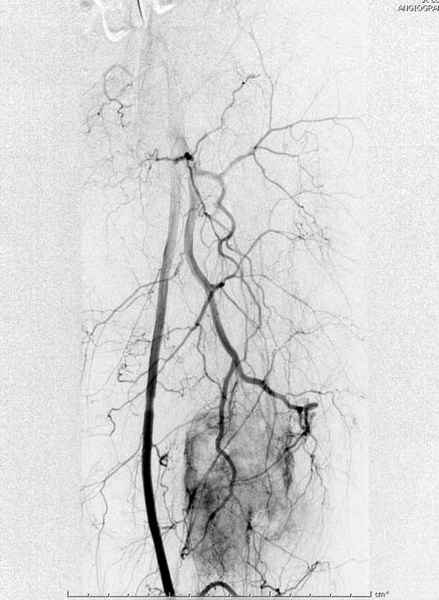

В зависимости от характера опухоли некоторые патологические переломы имеют риск кровотечения во время операции. Множественные литературные данные подтверждают, что надо проявить осторожность при интрамедуллярном остеосинтезе при неизвестных опухолях, особенно где имеется подозрение на Renal Cell Carcinoma. (RCC- hypernephroma) http://www.bonetumor.org/tumors/pages/page64.html

Для предупреждения кровотечения во время рассверливания, за день до операции провели эмболизацию сосудов питающий метастаз. http://radiology.rsnajnls.org/cgi/reprint/150/3/673.pdf (7-11, 12-15-16)

Кровопотеря во время операции меньше 100 мл.

По поводу "модной" тяги к "гвоздям" - это вы правы. А касательно эмболизации - просто СУПЕР!!!!,... никогда бы не допер. Просто ВАУ, нет слов.